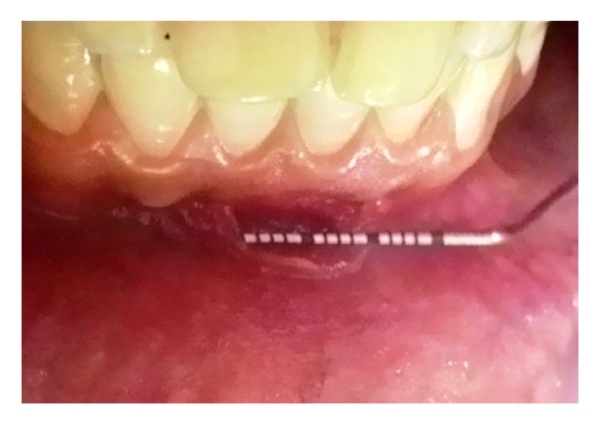

A 25-year-old male presented to the Department of Periodontics and Oral Implantology, Institute of Dental Sciences, Bhubaneswar, with a chief complaint of bleeding and pain in gums in the mandibular anterior region two weeks back. He admitted to have been scratching in the same region frequently with his fingernails on having sensitivity and irritation (Figure 1) which gave him a temporary relief. Occasionally, he used a matchstick in the same area till bleeding occurred and he felt relieved. On asking he revealed that he had lost his job four months back and was quite disturbed for the same reason. He further confided that he was feeling low and was depressed. Physically, he appeared emaciated and weak. His medical history was noncontributory and he was not currently under any medications.

Intraoral examination revealed erythematous gingiva in the area of chief complaint which bled profusely on probing. Also, it was partially detached with an irregular border giving a cleft-like appearance extending beyond the mucogingival junction in relation to mandibular right central incisor. He maintained poor oral hygiene with evidence of extrinsic stains, plaque, and calculus. No other pathological changes were seen in the oral cavity. He was then referred to the Department of Psychiatry, IMS and SUM Hospital, Bhubaneswar, where his SIB was confirmed. Therefore, a diagnosis of gingivitis artefacta major was made based on his history and clinical findings.